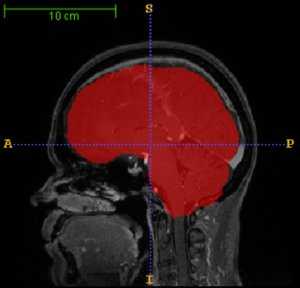

Skull-stripping (or brain extraction) is an important pre-processing step in neuroimage analysis. This document describes a skull-stripping filter implemented using the Insight Toolkit ITK, which we named itk::StripTsImageFilter. It is a composite filter based on existing ITK classes. The filter has been implemented with usability, robustness, speed and versatility in mind, rather than accuracy. This makes it useful for many pre-processing tasks in neuroimage analysis. This paper is accompanied by the source code, input data and a testing environment.